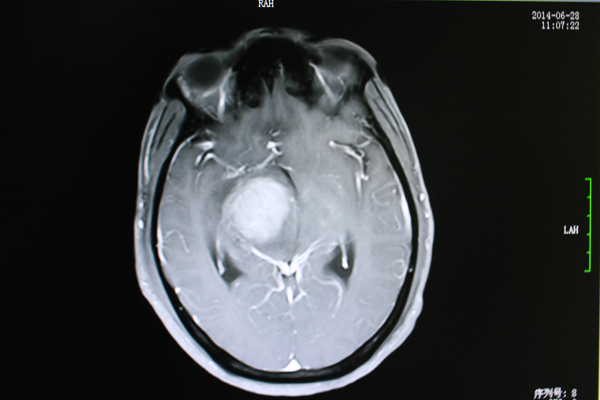

在南宁一家医院进行MRI检查后,黄先生被告知:桥脑、右侧大脑脚及右侧基底节区占位。也就是大脑的重要功能区长出了一个肿瘤。

8月12日,从最新的MRI检查结果上显示,病灶水肿范围较之治疗前明显缩小。

主管医生姜盛强介绍肿瘤治疗效果的标准:“有五个层面,包括恶化(肿瘤继续增大);无变化(肿瘤缩小在25%以下);微效(肿瘤缩小在25%-50%之间);有效(肿瘤缩小在一半以上);显效(肿瘤病灶消失)几个等级。”

“黄先生属于有效,也就是从肿瘤已经明显缩小,肿瘤对脑部神经和组织的压力减小。”

治疗前